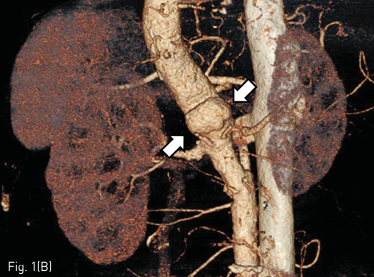

조영증강 CT에서 1.4 x 2.4 cm 크기의 낭성동맥류가 상부 복부 대동맥에서 보이고 상장간막동맥의 기시부 뒤쪽에 위치하고 있었다 (Fig. 1A-B). 그리고 우측 신장동맥 기시부에 국소 협착이 있었다.

Fig 1B

(A-B) Contrast enhanced CT and volume rendering image show a saccular aneurysm (arrows) involving the upper abdominal aorta, just posterior to the SMA origin.